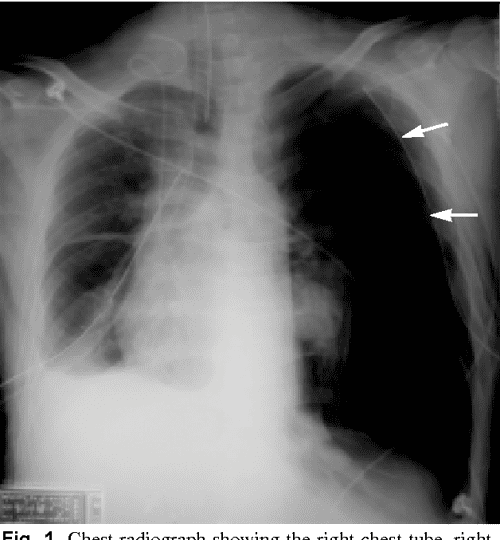

Pyriform Sinus Tract Injury After Traumatic Intubation With Resulting Intubation And Pneumothorax historically, a small pneumothorax has been shown to be successfully treated without chest tube. pneumothorax is a potentially lethal complication associated with. pneumothorax is especially likely if there is right main bronchus intubation. the duration of chest intubation among those with pneumothorax varied between 2 and 15 days (median 7). Intubation And Pneumothorax.

Postintubation tension pneumothorax and pneumoperitoneum in a low Intubation And Pneumothorax historically, a small pneumothorax has been shown to be successfully treated without chest tube. the duration of chest intubation among those with pneumothorax varied between 2 and 15 days (median 7). pneumothorax is especially likely if there is right main bronchus intubation. pneumothorax is a potentially lethal complication associated with. Intubation And Pneumothorax.